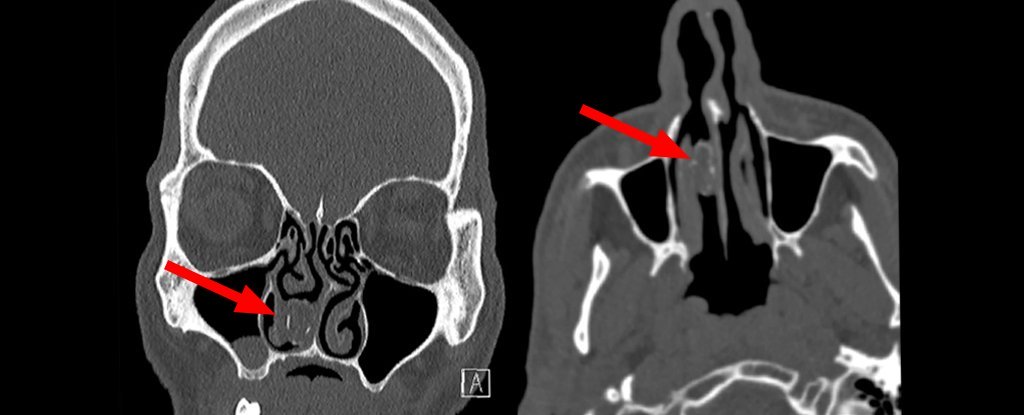

这名48岁男子日前因头痛到医院接受脑部断层扫描,意外发现鼻腔内居然有一块19毫米长、11毫米宽的鼻结石(rhinolith)。

医生说,*麻大**在男子鼻腔内发生钙化病变,才成为鼻结石,导致出现鼻塞、头痛、脸部疼痛和流鼻涕等症状。

医师为男子进行全身麻醉,顺利从鼻腔中取出陈年“包裹”,如今已经是一坨混杂着腐烂植物的异物。在除去结石后3个月,男子鼻子不适的症状已经缓解很多。